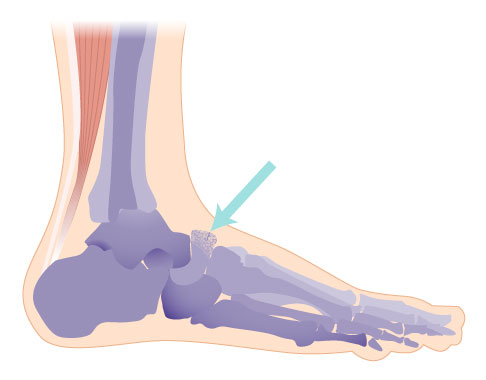

Vergleich eines gesunden Talonavikulargelenks mit einer Osteonekrose des Kahnbeins bei Müller-Weiss-Syndrom. Das vordere untere Sprunggelenk zwischen Kahnbein (Os naviculare) und Sprungbein (Talus) ist unmittelbar mitbetroffen. © Gelenk-Klinik

Darstellung der Fußwurzelknochen: Das Kahnbein (Os naviculare) ist durch seine knorpeligen Gelenkflächen mit den drei Keilbeinen (Os cuneiforme), dem Würfelbein (Os cuboideum) und dem Sprungbein (Talus) verbunden. Es ist Teil des unteren Sprunggelenks. © Gelenk-Klinik